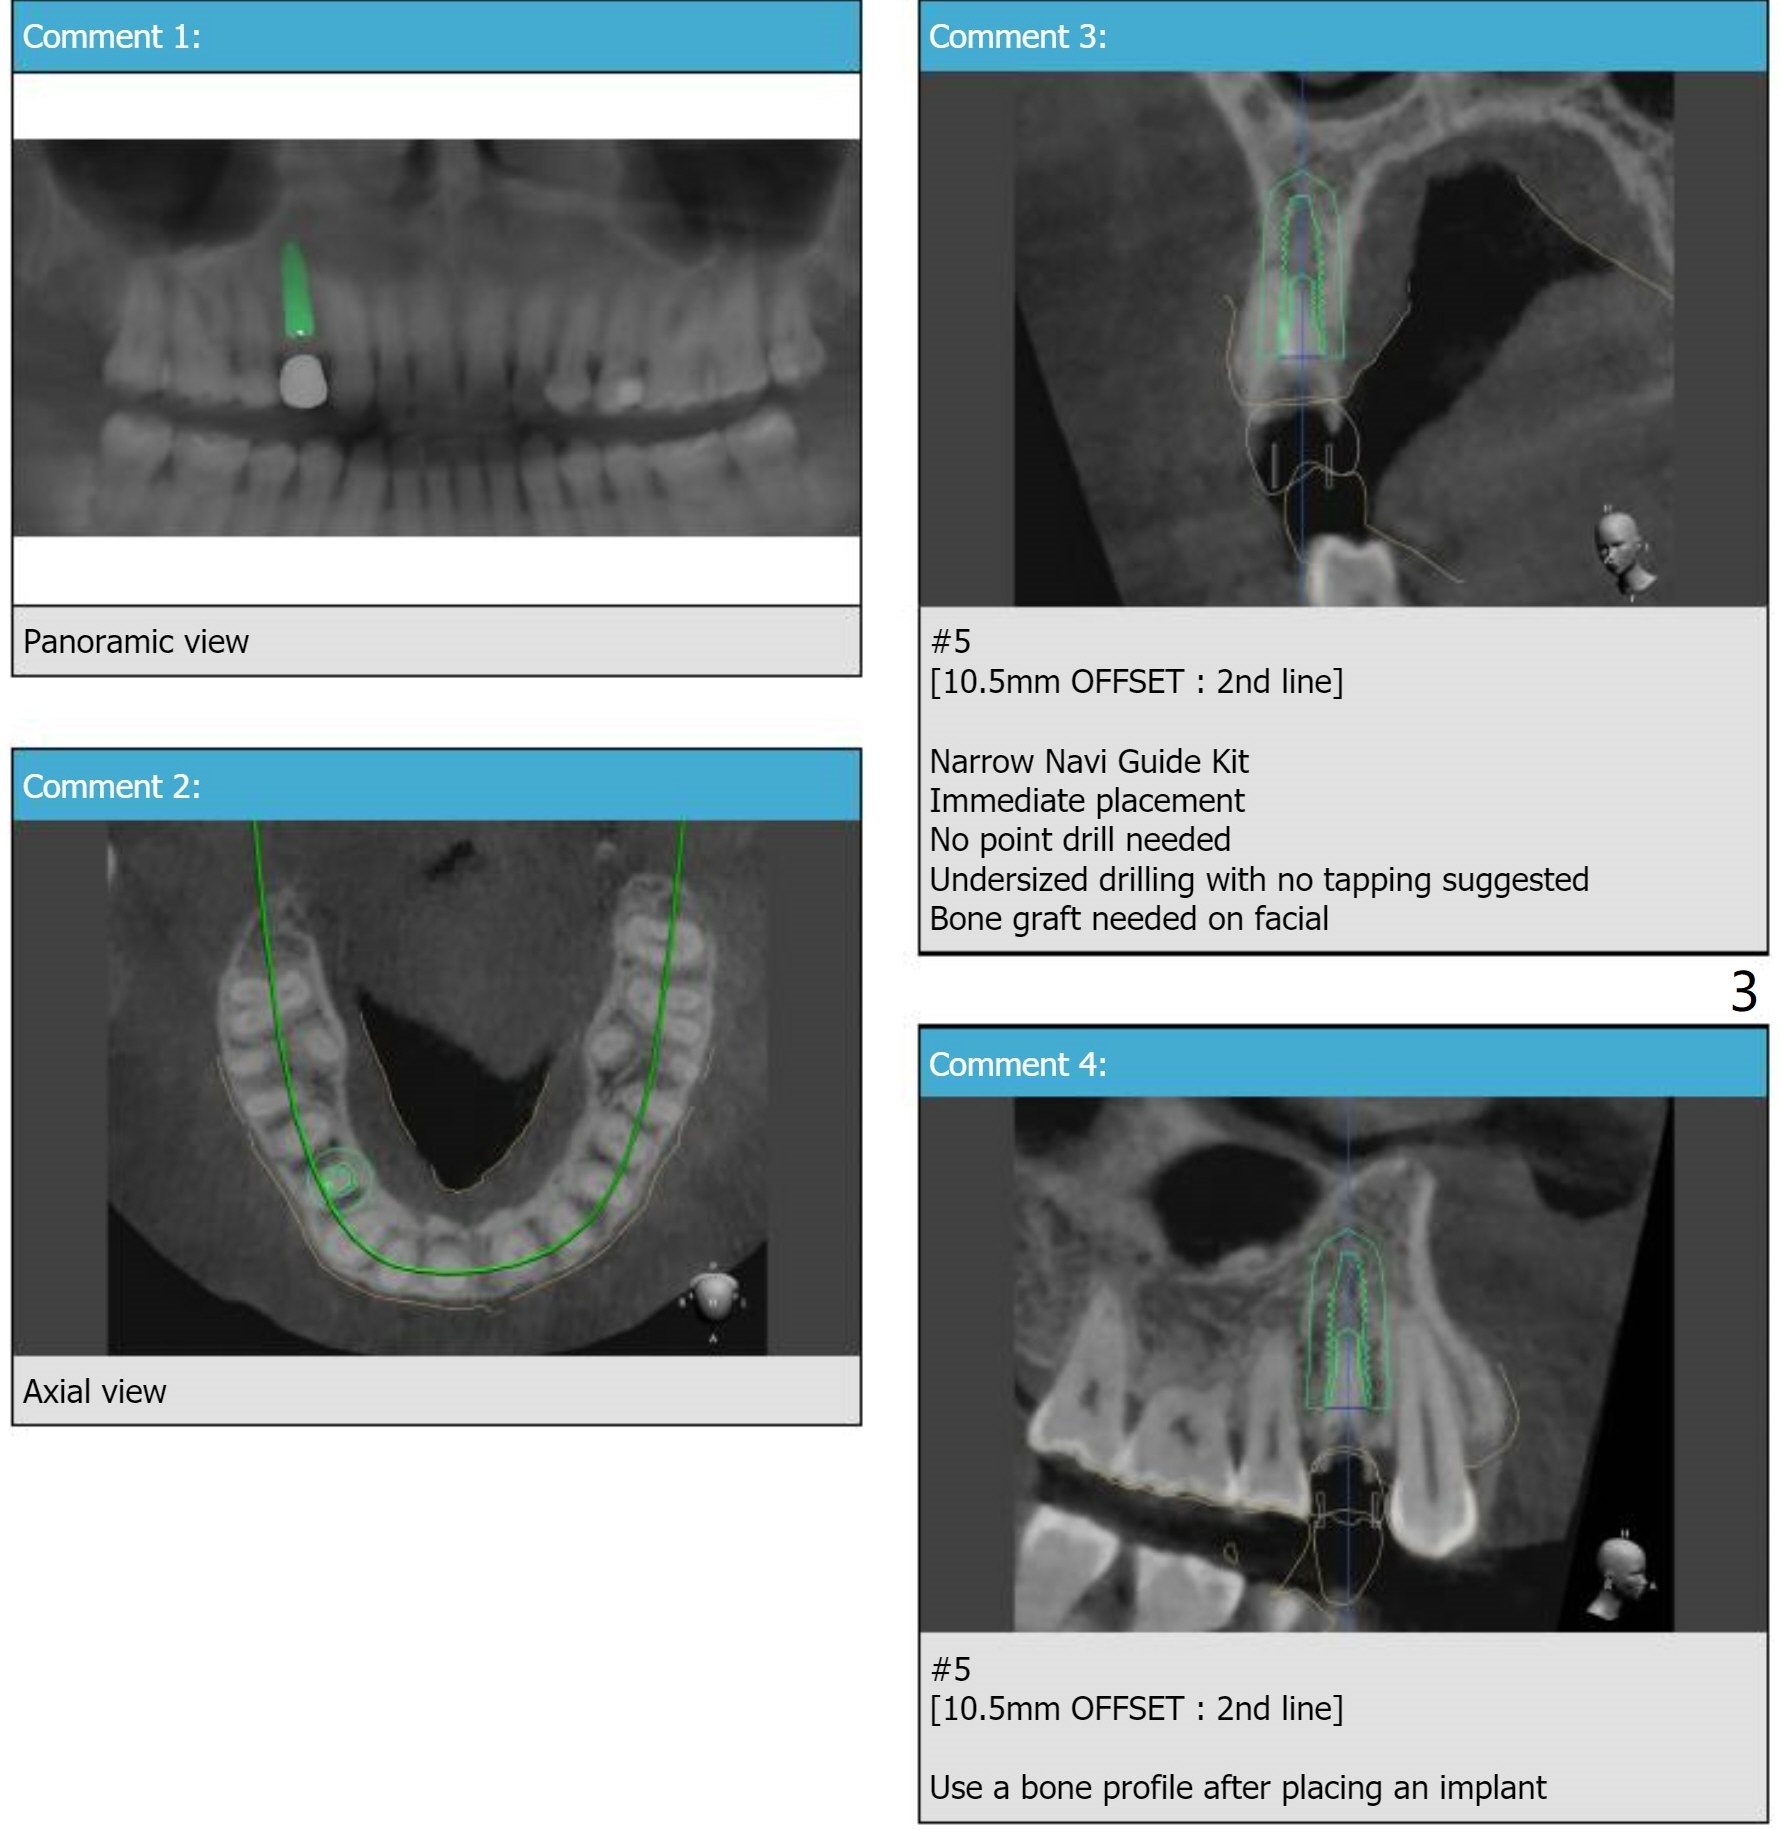

A 46-year-old woman

Xin Wei, DDS, PhD, MS 1st edition 06/28/2021, last revision 07/24/2021